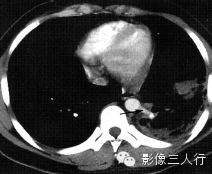

先天性肺囊肿(图3) | 棘球蚴病

(图4) |